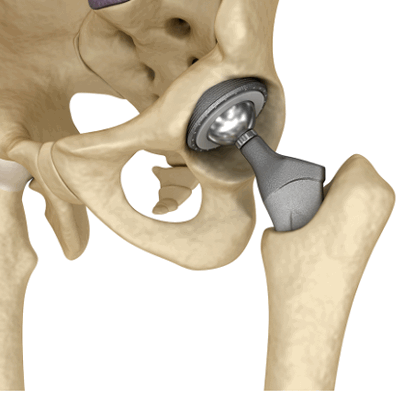

Эндопротезы коленного сустава

Коленный сустав

Тазобедренный сустав

Томография — информативный и безопасный метод изучения области ягодиц, бедер. МРТ с эндопротезом тазобедренного сустава проводят по следующим показаниям:

скопление жидкости в окружающих тканях (при недостаточной информативности КТ и УЗИ);

подозрение на септические осложнения в результате протезирования;

диагностика туннельного синдрома;

подозрение на поражение сухожилий в области сочленения.

Вариант протеза тазобедренного сустава